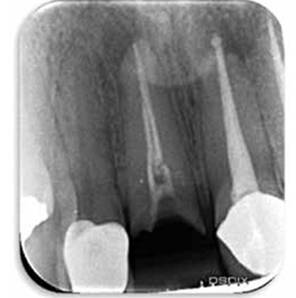

Seguidamente se coloca anestesia al 2%, para realizar exploración profunda y determinar de qué tamaño era el fragmento de corona separado y determinar si era posible su reposicionamiento y posterior restauración. (Figuras 5A ,5B y 5C)

Figura 5A: Remoción de corona.

Figura 5B: Remoción de corona Vista Radiográficamente,nótese la lesión periapical que tiene la pieza y el mal sellado del conducto.

Figura 5C: Porción coronal removida,obsérvese el fragmento radicular adherido a la corona.